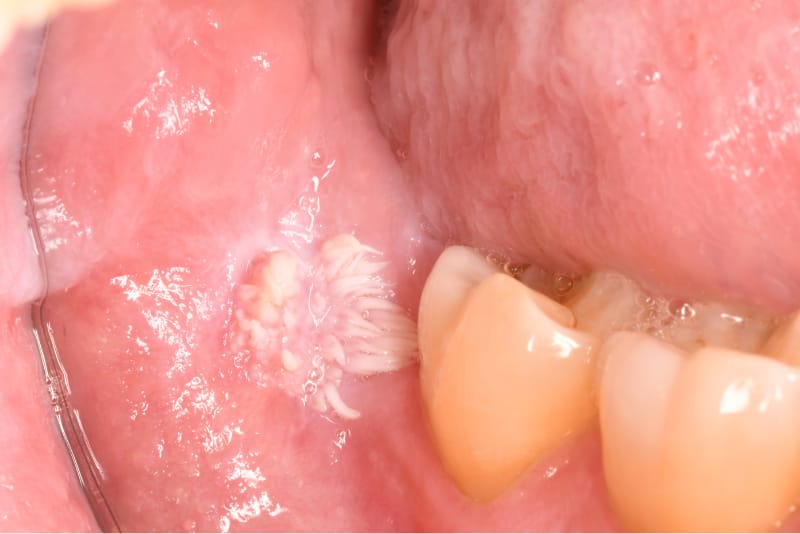

“Papilloma.”

This lesion was quite large, and therefore concerning. Fortunately, upon pathologic review, this lesion was benign.